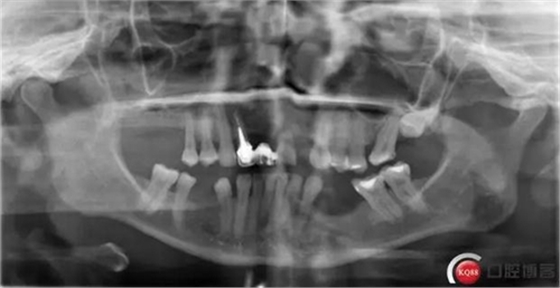

首頁流程步驟方法 種植體和下頜頦神經(jīng)“近距離接觸”一例 科貿嘉友收錄

種植體和下頜頦神經(jīng)“近距離接觸”一例 科貿嘉友收錄

看了黃生醫(yī)生的 “一例避開下齒槽神經(jīng)管種植病例 “ 一文, 想起自己有一例植體靠近下頜頦孔的病例。找出來和大家分享一下。